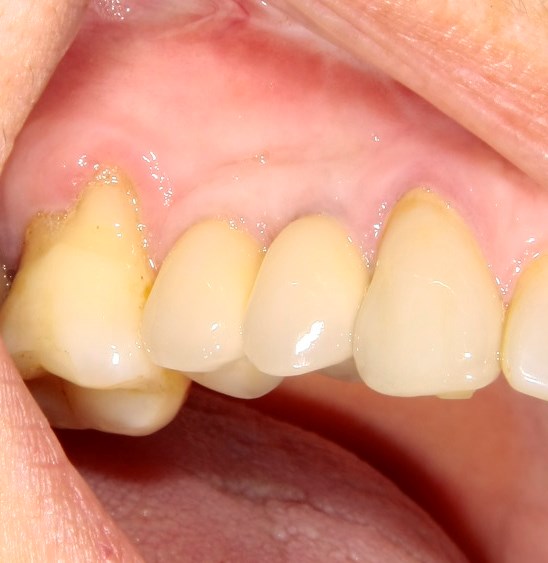

Опыт применения коллагеновой матрицы Mucograft в клинической практике.